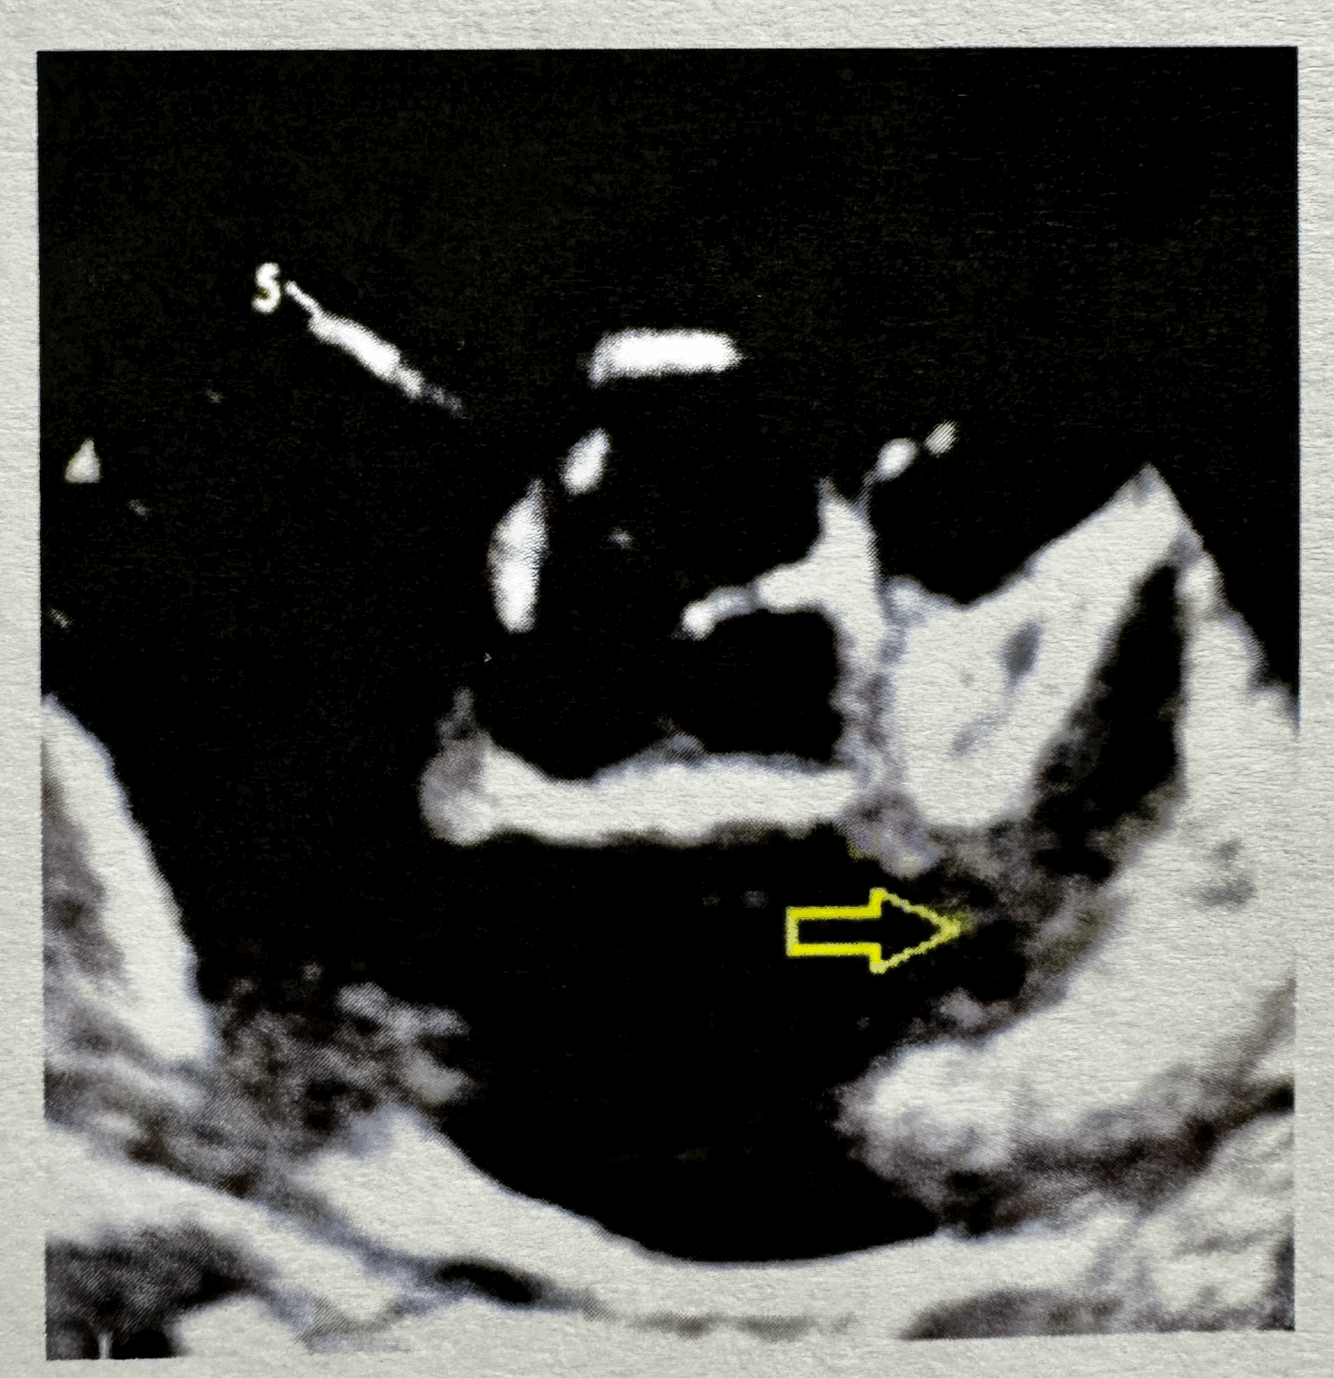

Q

What does the arrow reveal?

A

LV false tendon